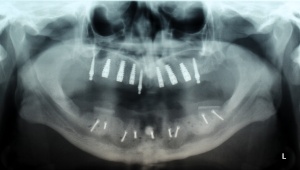

Im August 2012 erfolgten die 3D-gestützte Implantation (6 Implantate, Firma Nobel Biocare, System Active) im Oberkiefer mit Bone Split sowie eine An- und Auflagerungsosteoplastik vom linken Beckenkamm im Unterkiefer nach Entfernung der Miniimplantate (Abb. 3). Nach komplikationsloser Einheilung wurde im Dezember 2012 die Materialentfernung und Implantation im Unterkiefer (6 Implantate, Firma Nobel Biocare, System Active) durchgeführt (Abb. 4). Die Osseointegration verlief ungestört. Aufgrund der ungenügenden Weichgewebssituation im Unterkiefer erfolgte an jedem Implantat bei Freilegung eine Vestibulumplastik mit Einlagerung einer bioresorbierbaren Membran (Firma Botiss, Mucoderm, Abb. 5 und 6). Die endgültige prothetische Versorgung erfolgte durch den truppenzahnärztlichen Kollegen in der Stammeinheit des Patienten (Zahnarztgruppe Nordholz / SanZ Celle) mit einer gaumenfreien implantatgetragenen Teleskopprothese im Ober- und Unterkiefer, die eine festsitzend-herausnehmbare vollständige stomatognathe Rehabilitation des Patienten ermöglichte (Abb. 7 und 8). Er wurde zum halbjährlichen Recall angehalten.